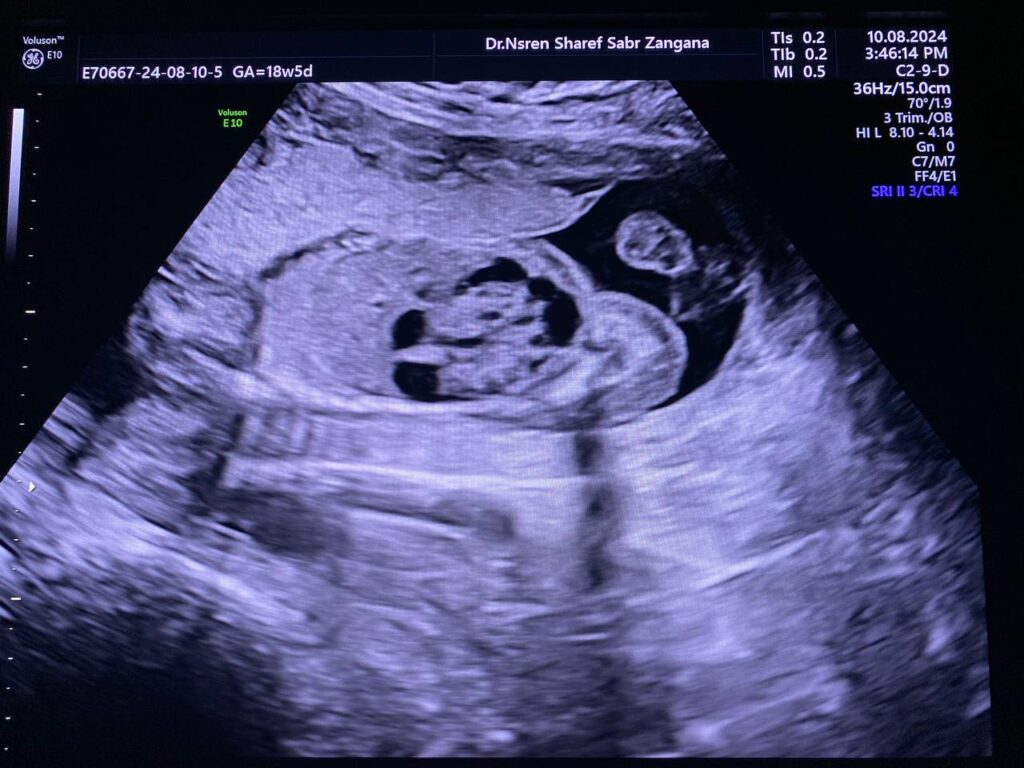

Same fetus when become about 19weeks

Right kidney enlarge in size 34x21x29mm, occupy by numerous

cysts of variable sizes, the largest 13mm , normal left kidney , polycystic ?